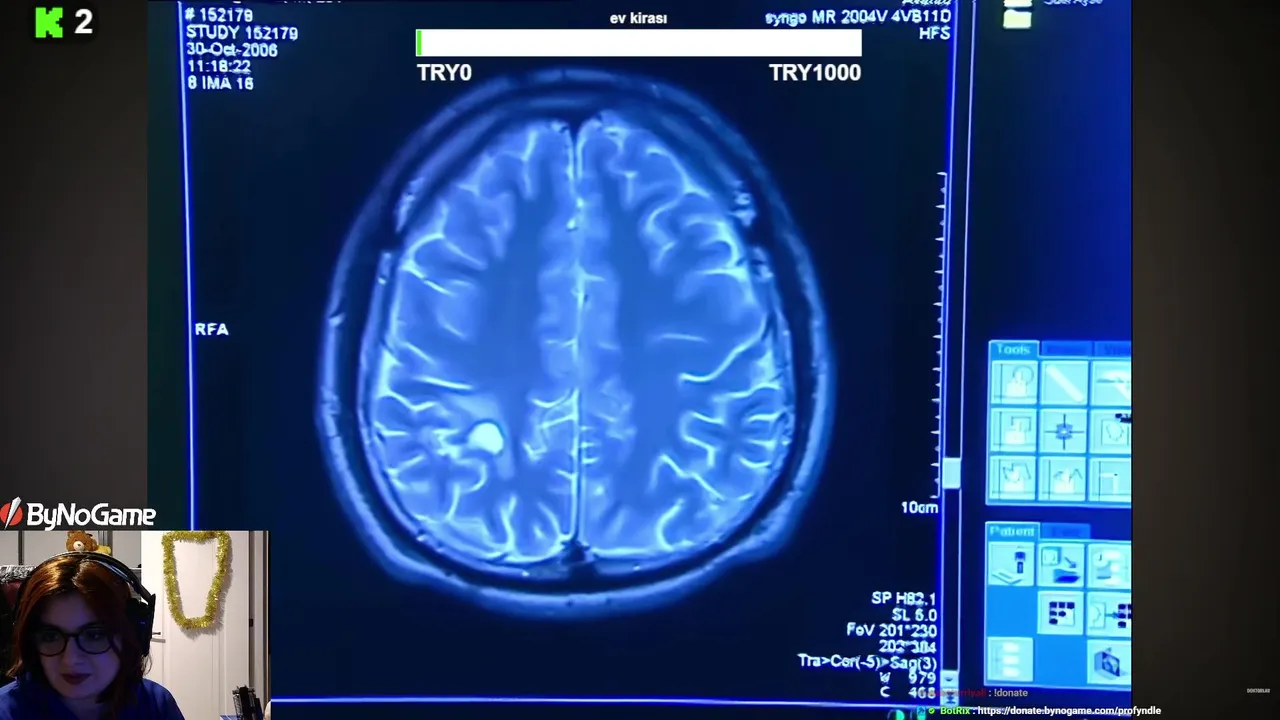

4503

profyndle

on kick.com

profyndle

on kick.com

Viewers: 4

Duration: 7 min. -